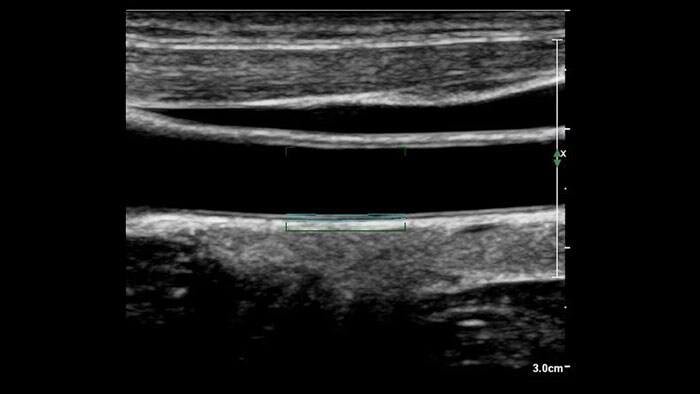

Support in determining cardiovascular disease risk

US Q-App Intima Media Thickness (IMT) provides easy and consistent measurement of intima media thickness in carotids and other superficial vessels. Report IMT values and append them to patient reports.